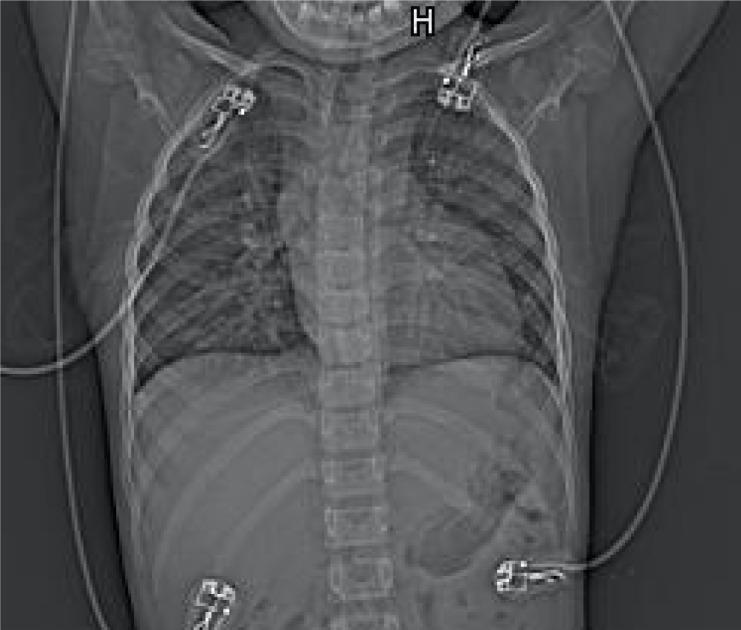

Herein, we report the anesthetic management of a 10-year-old female patient with a DORV. She lived in the low-oxygen Qinghai-Tibet Plateau, and presented with severe polycythemia (hemoglobin, 24.8 g/dL; hematocrit, 75%). She underwent a modified Fontan surgery, which was satisfactory and without any perioperative complications. Our anesthetic management highlights the importance of perioperative hemodilution in decreasing the risk of thromboembolism and the importance of correcting coagulopathy in preventing hemorrhage.

在此,我们报告一名10岁DORV女性患者的麻醉管理情况。她生活在低氧的青藏高原,患有严重红细胞增多症(血红蛋白24.8 g/dL;血细胞比容75%)。她接受了改良Fontan手术,手术效果满意,围手术期无任何并发症。我们的麻醉管理突出了围手术期血液稀释在降低血栓栓塞风险方面的重要性以及纠正凝血障碍在预防出血方面的重要性。